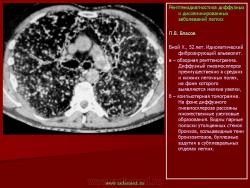

П.В. Власов

При идиопатическом фиброзирующем альвеолите на рентгенограммах обычно выявляется двустороннее симметричное усиление легочного рисунка. В противоположность саркоидозу, для которого характерно преобладание изменений в прикорневых отделах легких, при фиброзирующем альвеолите легочная ткань поражается более равномерно. Отмечено некоторое преобладание из менений в базальных и периферических, субплевральных отделах. Диффузная пролиферация фиброзной ткани ведет к деформации и перестройке архитектоники легочного рисунка по сетчатому типу. В периферических, субплевральных отделах легочный рисунок приобретает вид “пчелиных сот”, формируется картина так называемого “сотового легкого”: утолщенные межальвеолярные, периацинарные и междольковые перегородки охватывают эмфизематозно вздутые дольки и ацинусы. Для фиброзирующего альвеолита типичным является развитие буллезной эмфиземы, которая обычно развивается раньше других изменений легочного рисунка. Эмфизематозные буллы лопаются, вследствие чего иногда возникает спонтанный пневмоторакс, который может повторяться несколько раз. Одним из ранних рентгенологических проявлений идиопатического фиброзирующего альвеолита является диффузное понижение пневматизации типа матового стекла. C.Bergin с соавт. (1990) отметили, что при ИФА нередко наблюдается увеличение бронхопульмональных и медиастинальных лимфатических узлов. Следует однако иметь ввиду, что расширение корней легких при фиброзирующем альвеолите может быть вызвано увеличением калибра магистральных сосудов, вследствие гипертензии в малом круге кровообращения. Описанные признаки легочной гипертензии в далеко зашедшей стадии заболевания сочетаются с картиной так называемого легочного сердца. При фиброзирующем альвеолите вследствие уменьшения объема легких, диафрагма обычно занимает высокое положение. И.В. Васильчук (1985) отметила уменьшение объема легких и высокое положение диафрагмы с ограничением ее подвижности более чем у половины больных с идиопатическим фиброзирующим альвеолитом. Признаки легочной гипертензии отмечены у 30% больных. Нередко появляются дисковидные ателектазы. Функциональные исследования подтверждают наличие высокой степени респираторной недостаточности. Реография позволяет выявить признаки гипертензии малого круга кровообращения и дать ей количественную оценку. Сцинтиграфия может показать значительное понижение капиллярного кровотока, в местах наиболее выраженных изменений рентгенологической картины.